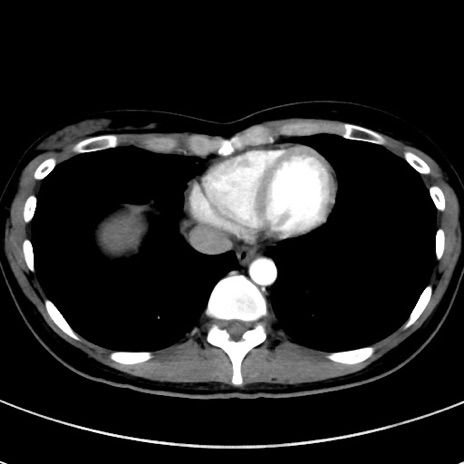

症例17(横断像)

【症例】20歳代女性

【主訴】嘔吐、下腹部痛

【現病歴】昨日夕食後に嘔吐し下腹部痛が出現。本日になっても嘔吐持続し改善しないため来院。

【身体所見】意識清明、BT 37.2℃、BP 108/67mmHg、腹部:平坦、やや硬、下腹部正中から右にかけて圧痛あり、反跳痛軽度あり、tapping pain(+)。

【データ】WBC 13600、CRP 14.94